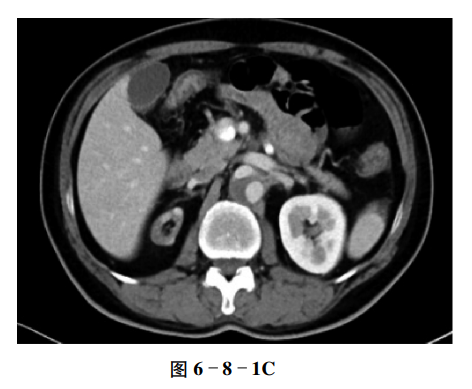

【CT征象】

平扫示右肾明显缩小,外观仍保持正常肾的形态,左肾代偿性增大(图6-8-1A),增强扫描示双肾皮质明显强化,髓质密度稍低,右肾的形态及排泄功能与左肾相似(图6-8-1B、C)。腹主动脉见夹层形成。

【重要征象】

右肾体积小,肾皮质和髓质密度、强化相对正常,"肾缩影征"。

CT表现

①多为单侧,表现为肾区小的软组织影,其肾实质、肾窦普遍缩小,可见肾盂,如正常肾的"缩影"。②肾动脉及输尿管细小,增强扫描肾实质强化,可见肾盂、肾盏内对比剂影。③对侧肾代偿性增大,皮质明显增厚。